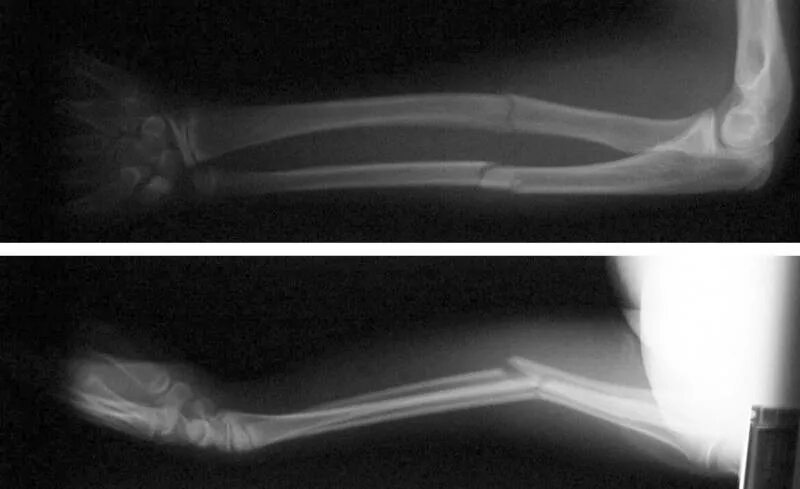

Перелом руки срок срастания